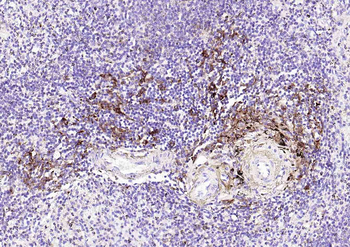

| Tested applications | IHC |

| Dilution range | Immunohistochemistry (Frozen & Formalin-fixed) (1-2ug/ml for 30 minutes at RT),(Staining of formalin-fixed tissues is enhanced by boiling tissue sections in 10mM Citrate Buffer, pH 6.0, for 10-20 min followed by cooling at RT for 20 minutes),Optimal dilution for a specific application should be determined. |

| Application notes | Positive Control: Human tonsil or lymph node |